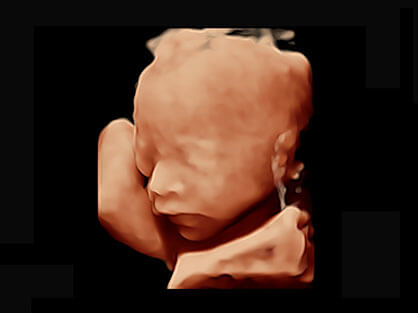

作为P系列家族成员之一,P40 Plus采用DB中国旗舰官方网站高端超声系统平台——极光,并以时尚秀丽、小巧灵动的外观设计绽放出灵动之韵、科技之美。高端平台的使用保证了P40 Plus优质的基础图像;完备的高级功能可满足您全身应用的基本需求;丰富的探头配置、多样的高级4D成像及分析软件为您日益增多的妇产应用需求提供丰富的诊疗方案。

宽频带腹部凸阵探头和腹部容积探头、大角度腔内探头和腔内容积探头、独特的生殖专用曲柄探头,为妇产应用提供全面诊疗方案。